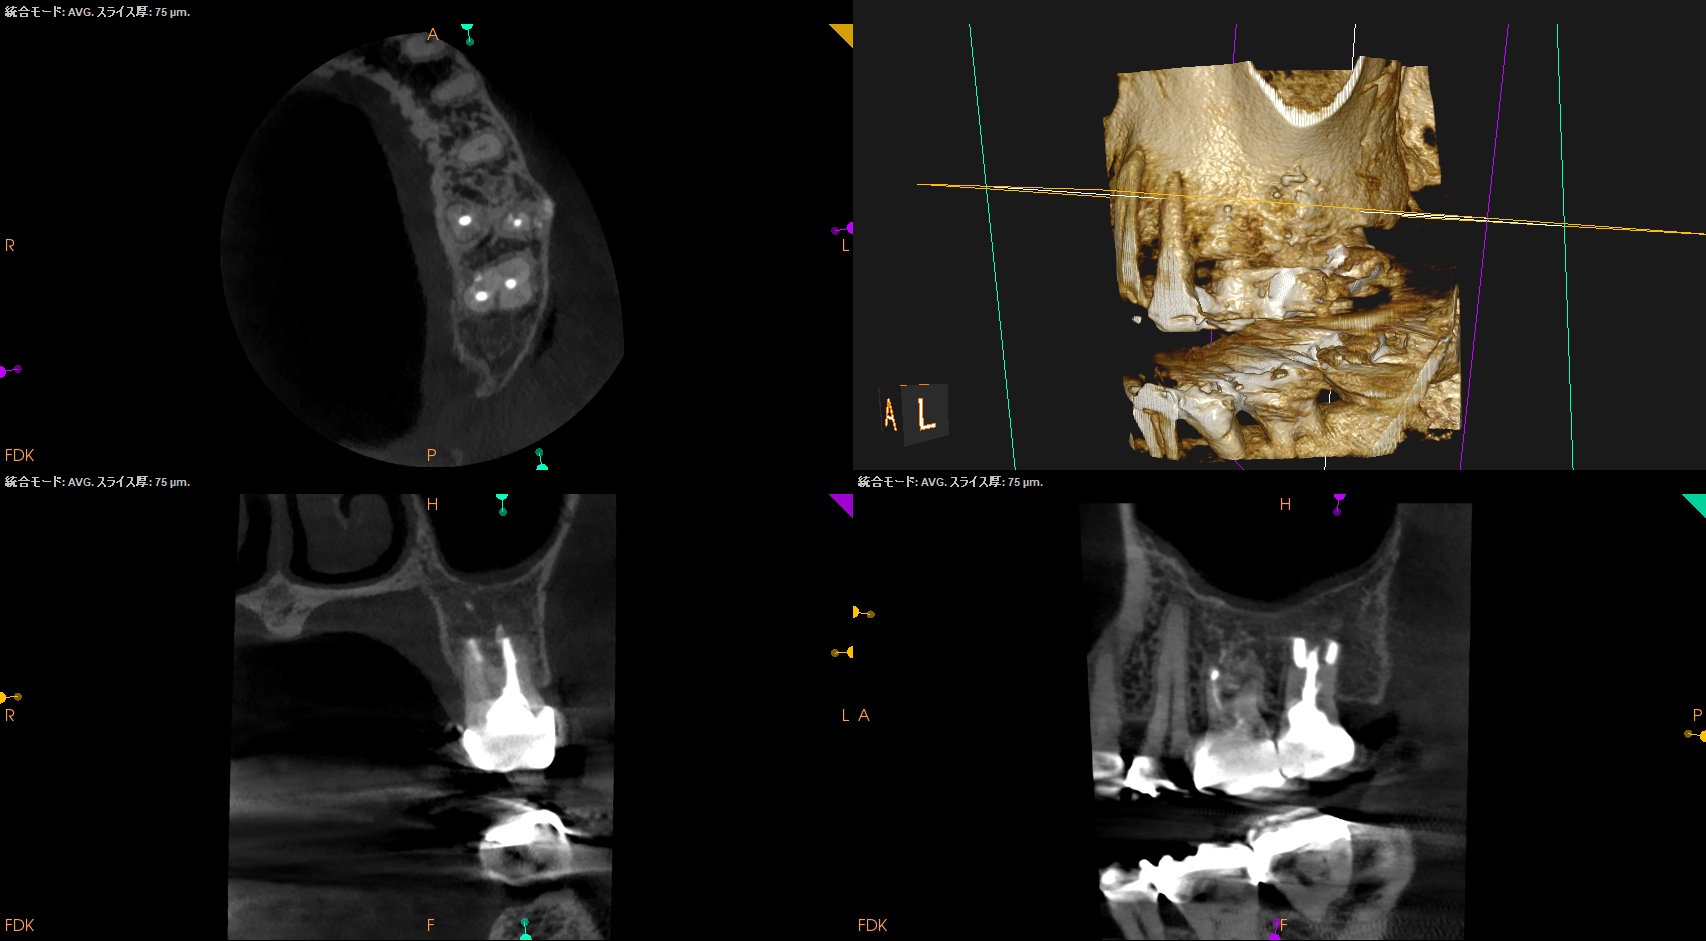

CBCT(2025.11.5)

MB

DB

P

Perforation site